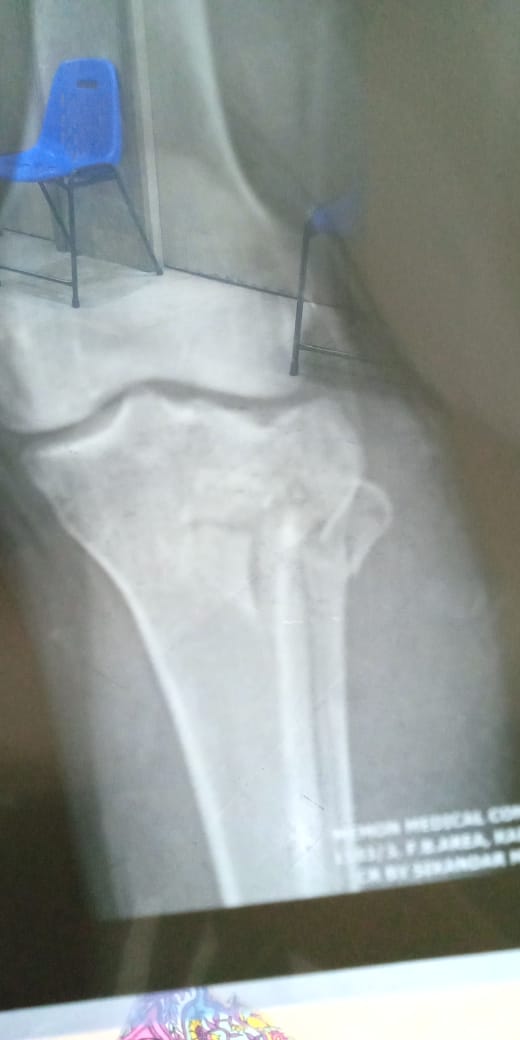

I had an accident on Thursday in which lateral condyle fracture occured.I want to ask it is need for surgery or plaster??

Attach Photo here: